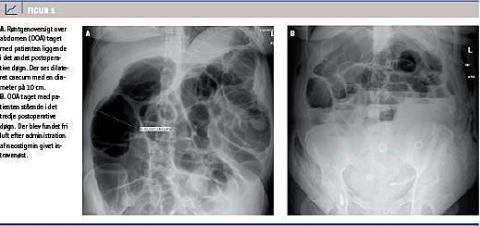

En 37-årig, gravid kvinde blev indlagt ved gestationsalder 29 uger + fem dage grundet kraftig vaginalblødning og delvis abruptio placenta. Det estimerede blodtab efter ankomst til hospitalet var 1.000 ml, og der blev foretaget akut sectio på vital indikation. Postoperativt blev patienten sat i behandling med intravenøst (i.v.) givet cefuroxim og metronidazol. Patienten var ved ankomst allerede i behandling med erytromycin, hvilket var påbegyndt af egen læge pga. pneumoni. Patienten havde det første postoperative døgn (POD) tiltagende diffuse abdominalsmerter, kvalme, opkastninger og flatus, men ingen afføring. En røntgenoversigt over abdomen (OOA) viste pseudoobstruktion med en caecumdiameter på 9 cm (Figur 1). Der blev ordineret sonde til svagt sug og flydende kost. En kontrol-OOA på 2. POD viste tiltagende caecumdiameter på nu 10 cm, og colonindhældning var uden mekanisk årsag. Jævnfør afdelingens instruks blev der ordineret neostigmin 2,5 mg givet i.v. over 5 min, hvilket medførte flatusafgang og klinisk bedring. En OOA på 3. POD blev af vagthavende bagvagt tolket som fortsat dilateret caecum, hvorfor der igen blev givet neostigmin i.v.. På en røntgenkonference dagen efter fandt man nytilkommen fri luft og subkutant emfysem, der var blevet overset på den seneste OOA (Figur 1B). Ved et efterfølgende kirurgisk tilsyn fandt man dog patienten afebril, oppegående og upåvirket med en leukocytkoncentration på 21,9 mia./l og et CRP-niveau på 187 mg/l. Hun blev herefter behandlet konservativt og under uændret antibiotisk behandling observeret tæt af seniorkirurger. Hun fik fuldkost og havde normaliseret tarmfunktion. En computertomografi (CT) af abdomen på det 7. POD viste ikke ansamlinger eller fri væske intraabdominalt. Efter normalisering af infektionsparametre på det 9. POD seponeredes den antibiotiske behandling, og den kirurgiske behandling af patienten blev afsluttet. Efterfølgende blev der ikke rapporteret om komplikationer.